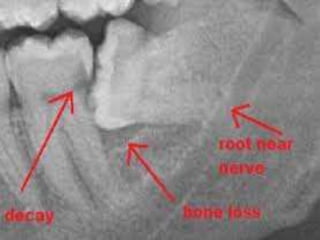

RADIOLOGICAL EVALUATION

The purpose of a careful radiological evaluation is to complement the clinical examination by providing

additional information about the third molar, the related teeth and anatomical features, and the surrounding

bone. This is necessary in order to make a sound decision about the proposed surgical procedure.

 the type and orientation of impaction and the access to the tooth.

 the crown size and condition

 the root number and morphology

 The alveolar bone level

 the periodontal status

 the relationship or proximity of lower third molars to the inferior dental canal.